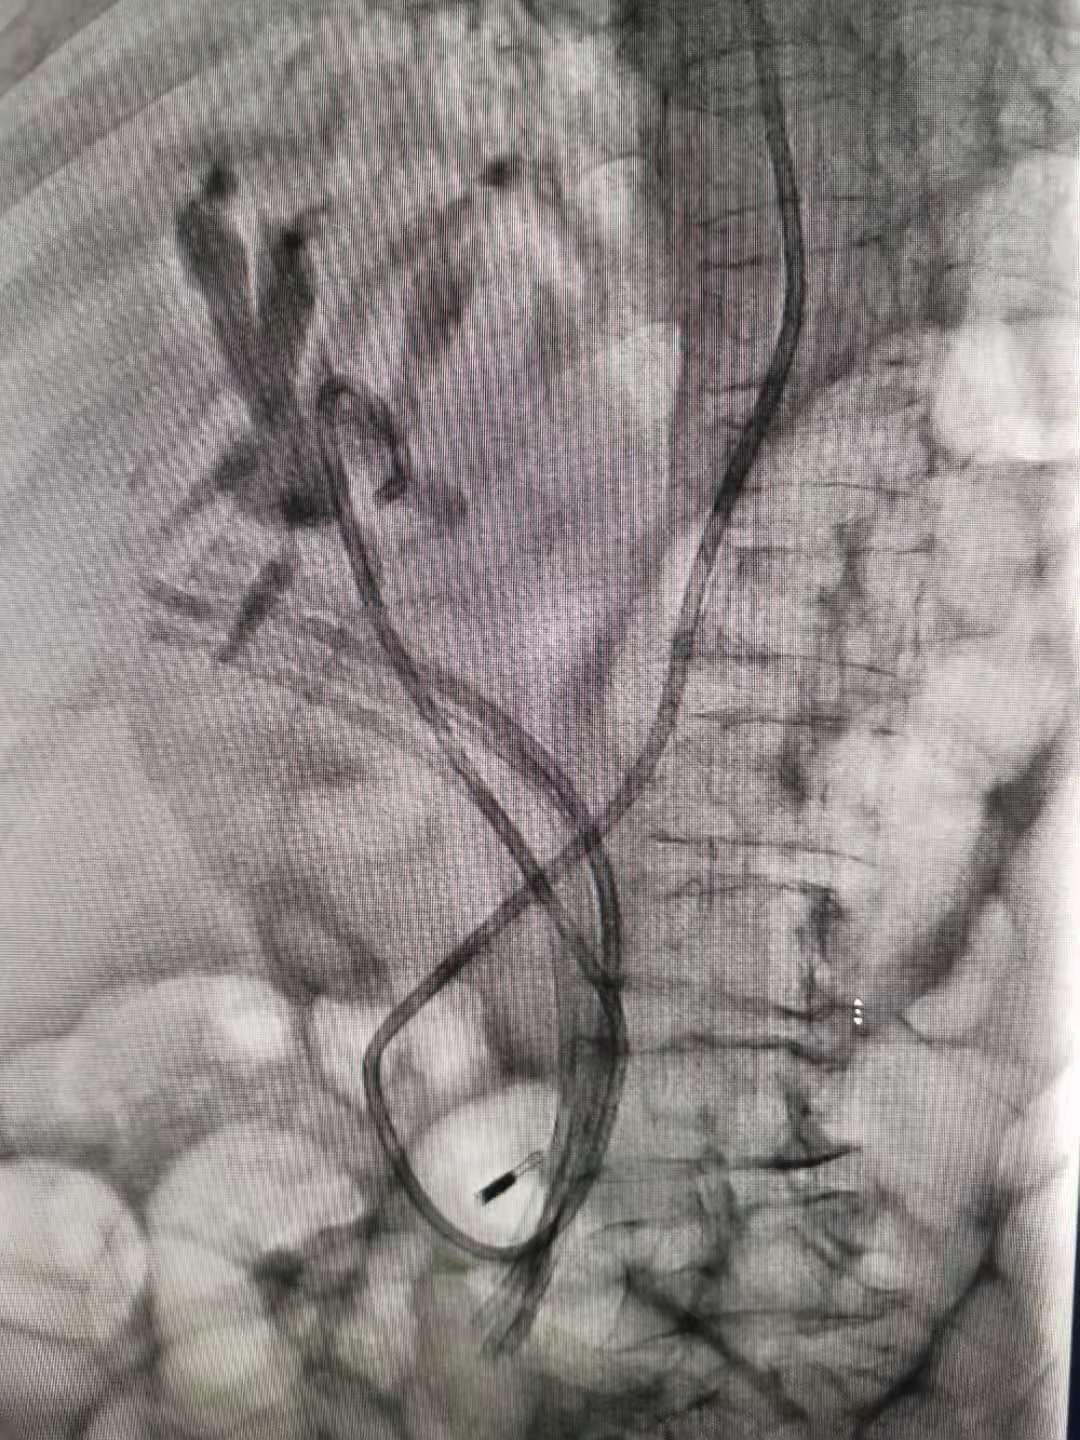

胆胰管开口在十二指肠降部,ERCP操作需将十二指肠镜从口腔插入患者体内,经食管、胃部至十二指肠降部、经十二指肠乳头注入造影剂,由于镜身盘绕及视线局限,很难前进,可谓每一毫米都需要调整定位,非常考验操作者的技术。经过反复探查找到李奶奶的嵌顿于胆总管内的(异物)塑料支架,章诺贝教授迅速插入取石网篮将其安全取出,同时见数枚大小不等的结石随之掉入十二指肠腔内,而结石最大者足有10毫米。术中并留置5根塑料支架于肝总管,为避免支架滑脱置入一枚和谐夹于乳头表面进行塑形,最后置入一根鼻胆道引流管于左肝管,胆汁引流通畅,全操作过程一气呵成,耗时五十分钟!

李奶奶在手术过程中不但没有明显不适感,术后没有出血、穿孔、胰腺炎等并发症,疼痛、腹胀等症状也很快消失,2天后便出院。她对治疗效果非常满意:“真的来对地方了,打了个盹的时间就把‘东西’取出来了!”